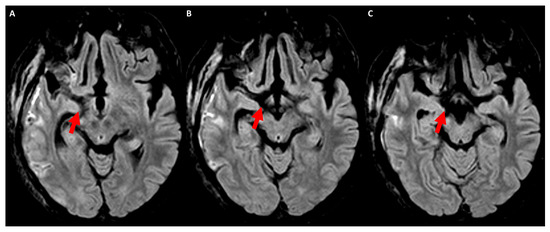

The hypointensity in T2WI in the subacute phase is mainly due to an alteration in protein–lipid–water content as a result of degradation and disintegration of the myelin sheath [29]. In the chronic stage of Wallerian degeneration, atrophy of the pyramidal tract can be detected by computed tomography, as documented in early studies [30]. On the contrary, transaxonal neurodegeneration (e.g., hypertrophic olivary degeneration) lacks DWI hyperintensity in any temporal phase of its evolution, with an early T2WI hyperintensity of the inferior olivary nucleus [31,32]. However, MRI does not show a lesion in 44% of cases of hypertrophic olivary degeneration [31]. An example of the signal changes in Wallerian degeneration in conventional MRI is provided in Figure 1.

Figure 1. Axial FLAIR MRI acquired at 4 weeks after ischemic stroke in the right middle cerebral artery territory because of endocarditis involving the posterior limb of the internal capsule within the territory of the left anterior choroidal artery. Panels (AC) show sequential slices from top to bottom at the level of the cerebral peduncle. The hyperintense signal (red arrows) corresponding to the course of the corticospinal tract is clearly evident on the right side in comparison with the normal signal on the left side.